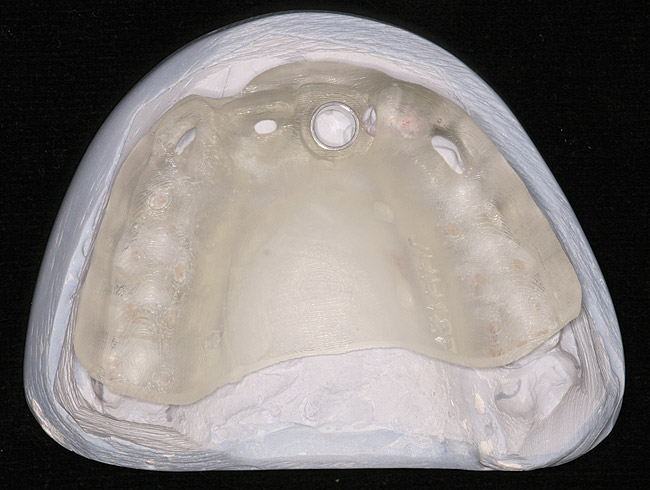

Figure 12  Preoperative mounted casts, complete maxillary extraction/immediate placement/immediate load patient.

Figure 12

Figure 13  Scan appliance, case in Figure 12.

Figure 13

Guided implant surgery involves reverse treatment planning. The ideal contour and arch position of the restoration is planned first, followed by virtual planning of the implant into that position according to the bony anatomy and clinical scenario. SLA surgical guides are then fabricated from the treatment plan. A dental laboratory next uses the SLA guide, with mounted casts, to fabricate provisional restorations prior to implant placement. At the time of surgery, the surgical guide is used to place the implants flaplessly, removing only a tissue core in the implant site(s). Abutments are immediately placed, and provisional restorations can be inserted.15-20 (Figure 12 through Figure 17).